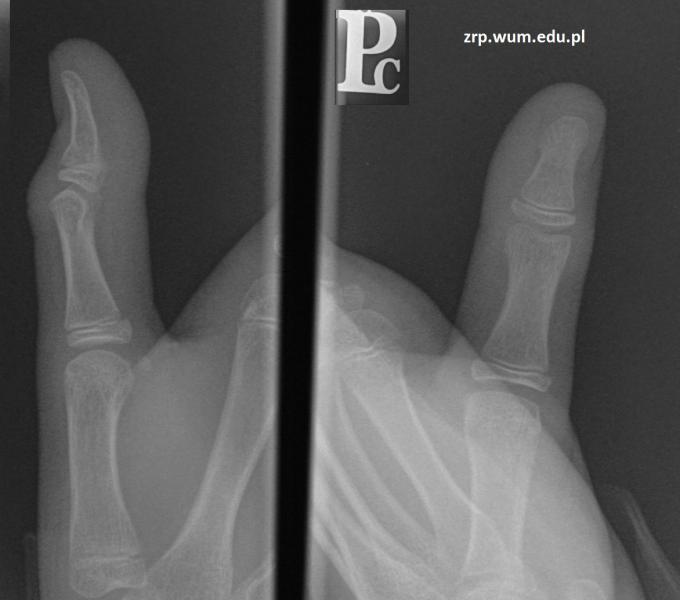

11-letni pacjent po urazie palca I-go ręki prawej

Przypadek 24: 11-letni pacjent po urazie palca I-go ręki prawej.

Rozpoznanie: W badaniu RTG stwierdzono złamanie przynasady bliższej paliczka dystalnego - ugięcie warstwy korowej od strony grzbietowej (strzałka).